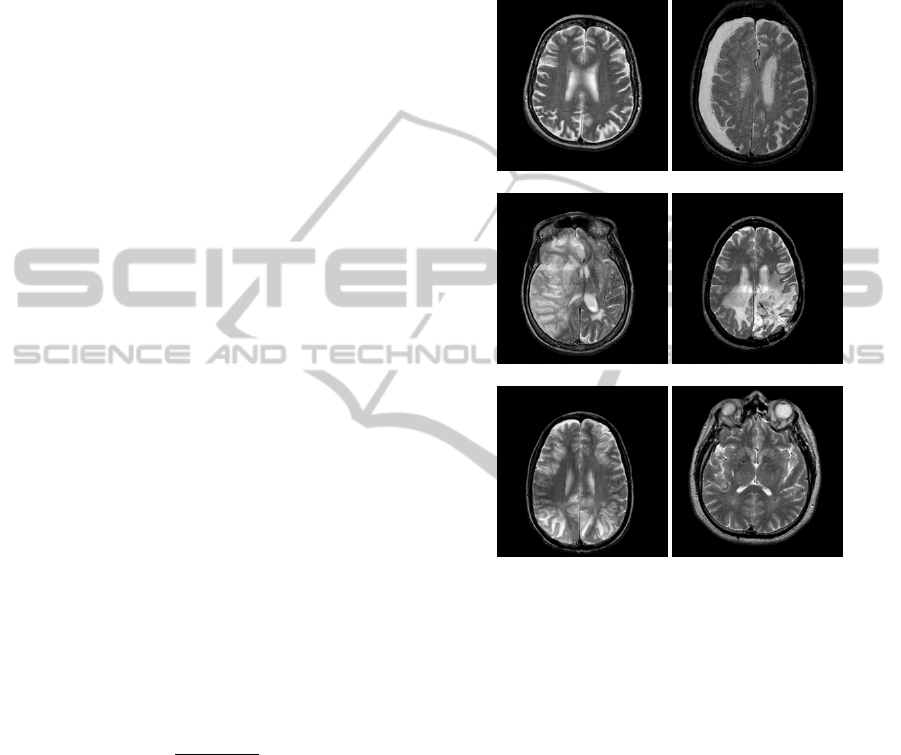

Figure 4: an example of a pertinent handcrafted

combination using the db2 wavelet: (a) the approximation

coefficients of the first UWT decomposition level of

Figure 2(b), (b) the approximation coefficients of the fifth

UWT decomposition level of Figure 2(b), and (c) result of

(a) minus (b). From (c), one can note that a large part of

the hematoma is highlighted (next to some other small

non-pertinent regions).